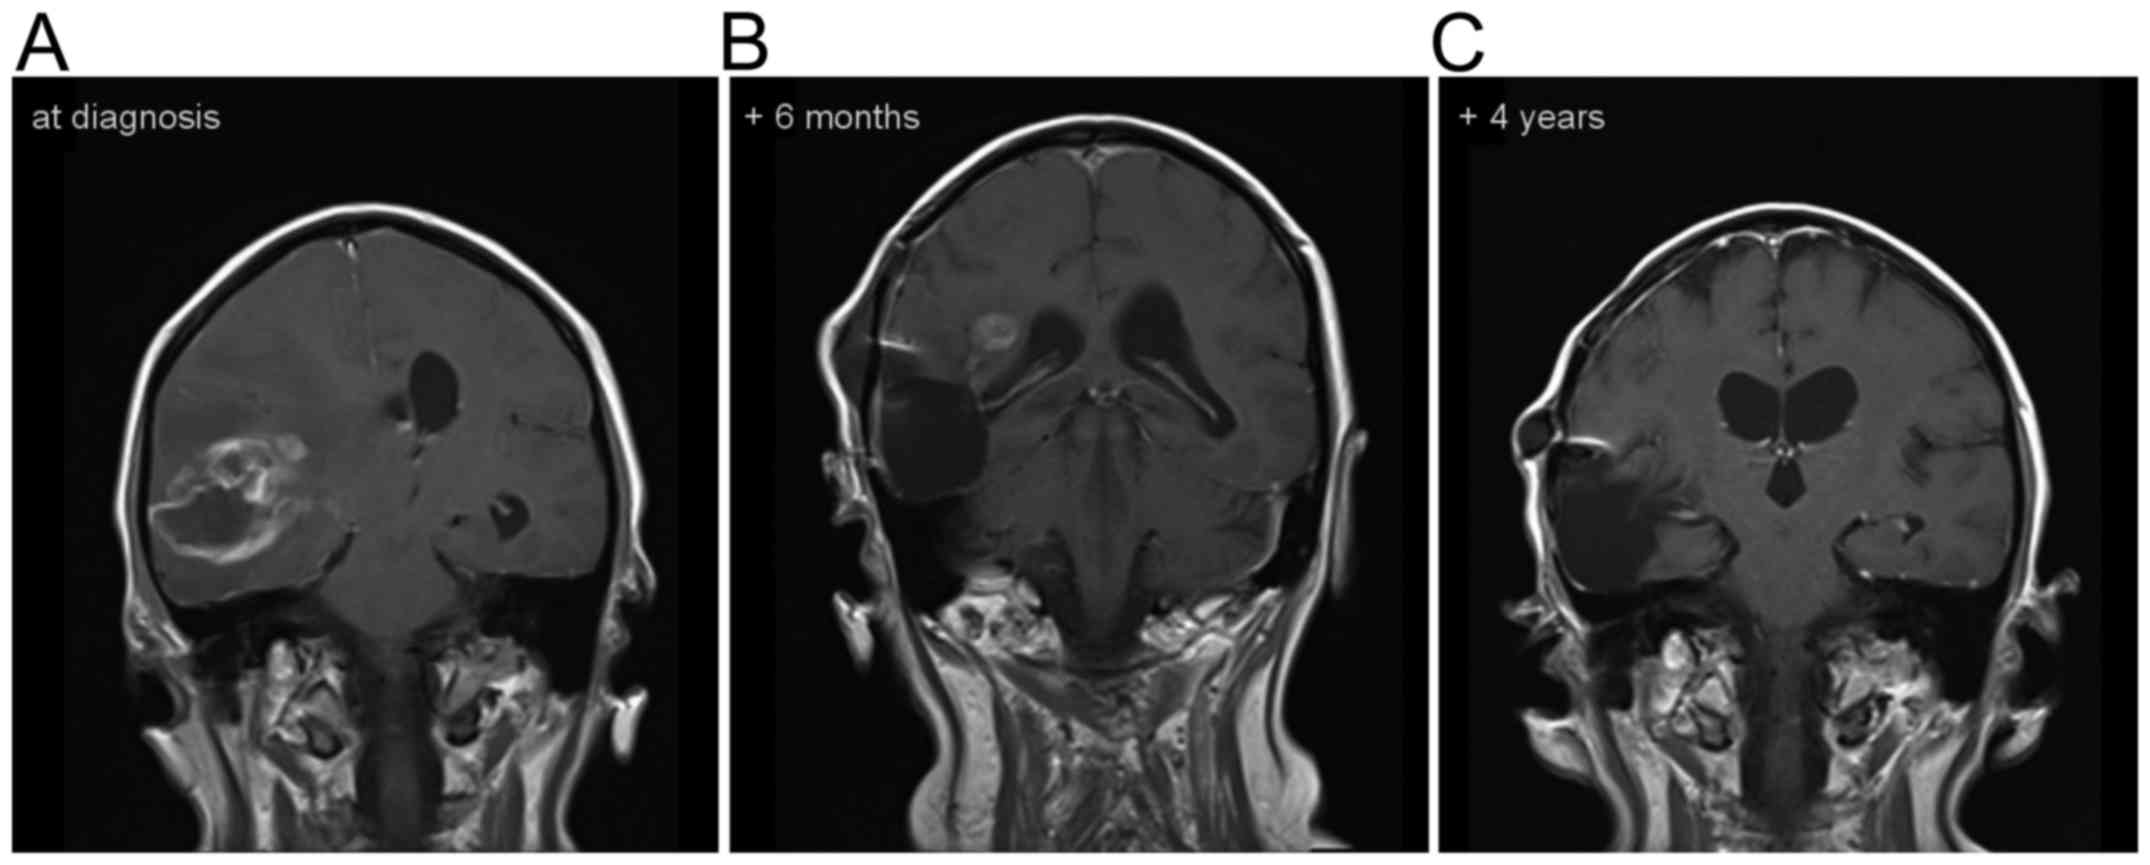

Figure 4.

Sagittal MR T1-weighted images post gadolinium images of Patient No. 3 in whom the O2-O3 treatment was started following the initial surgery and diagnosis of (A) GB. Six months later, some contrast enhancement was still visible (B), that was not apparent four years following diagnosis (C).

The median overall survival rate in our series comprising of five patients was 40 months. Since in one patient the O2-O3 treatment was started following diagnosis, the median survival following recurrence was 30.5 months (range, 12 to 37 months) in the remaining four patients. These data outperform previously published data (3) and the data from a recent multicenter trial including 505 patients from 20 institutions undergoing re-resection in recurrent GB (4). In that multicenter study, the median overall survival rate was 25 months and 11.9 months following the first resection. Furthermore, one of the patients in the present study treated with local O2-O3 in addition to the standard treatment following initial surgery remains alive, 53 months following the diagnosis of GB (Fig. 4A-C). The patients in our series did not differ substantially with regard to known prognostic factors: The median age at diagnosis was 48 years (range, 31 to 68 years), the median Karnofsky score at presentation 80% (range, 50 to 90%), the median proliferation index 30% (range, 20 to 40%) and the median quantitative MGMT promoter methylation was 5% (range, 3 to 25%).